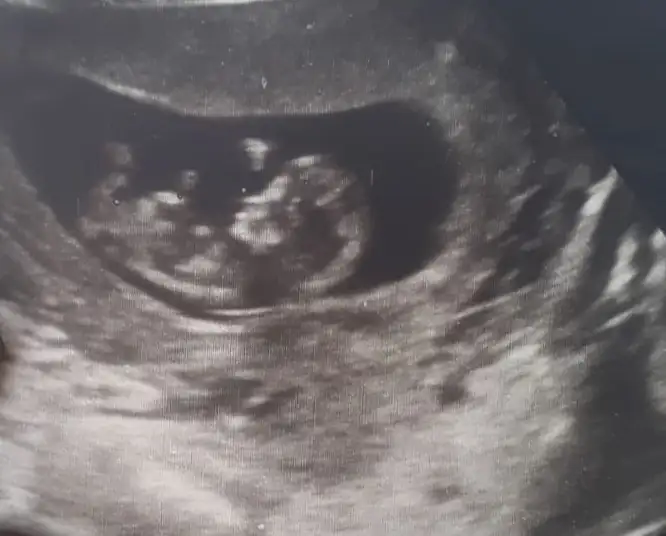

Eki Görüntüle 2543860 Merhabalar.Ikra meyra cim iyi akşamlar canım. Fotoğrafı yüklüyorum fikirlerinizi çok merak ediyorum :)